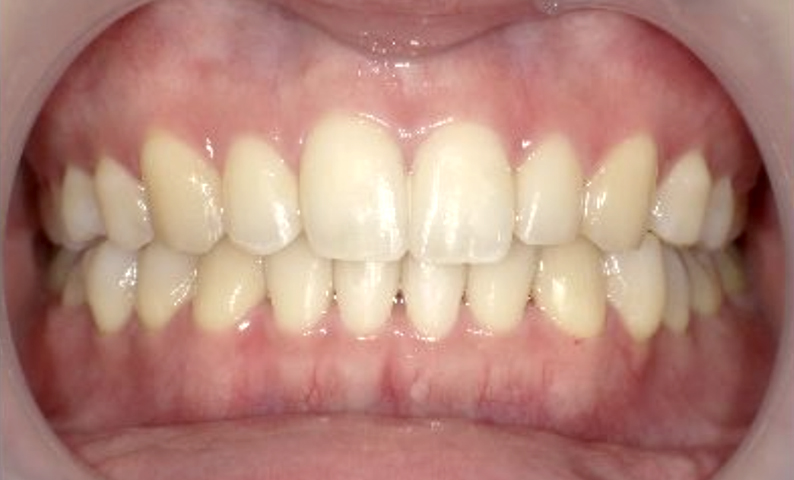

症例_001 下顎だけの部分矯正

治療期間:6ヶ月金額:27万円+税女性前歯のガタガタ下の前歯だけ

| Before | After |

|---|---|

|